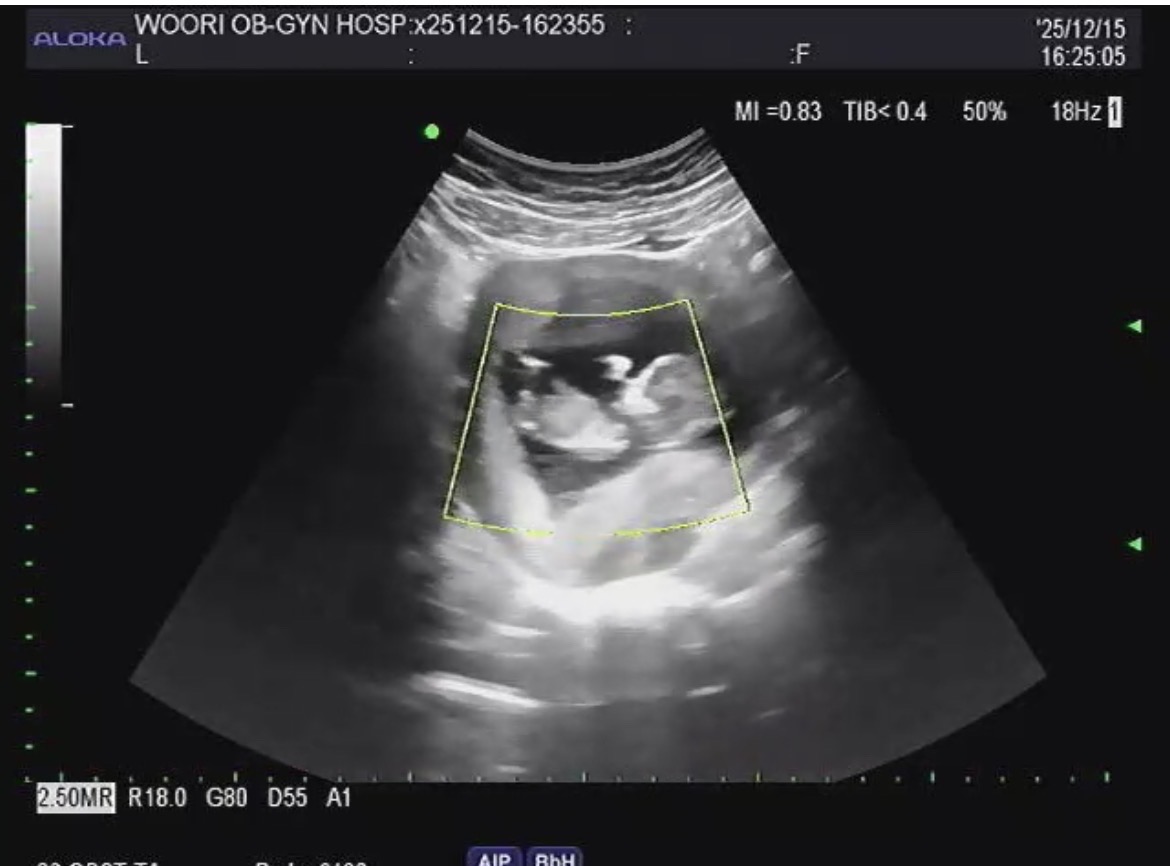

각도법 성별 봐주세요🥹🥹

남아일까요 여아일까요??